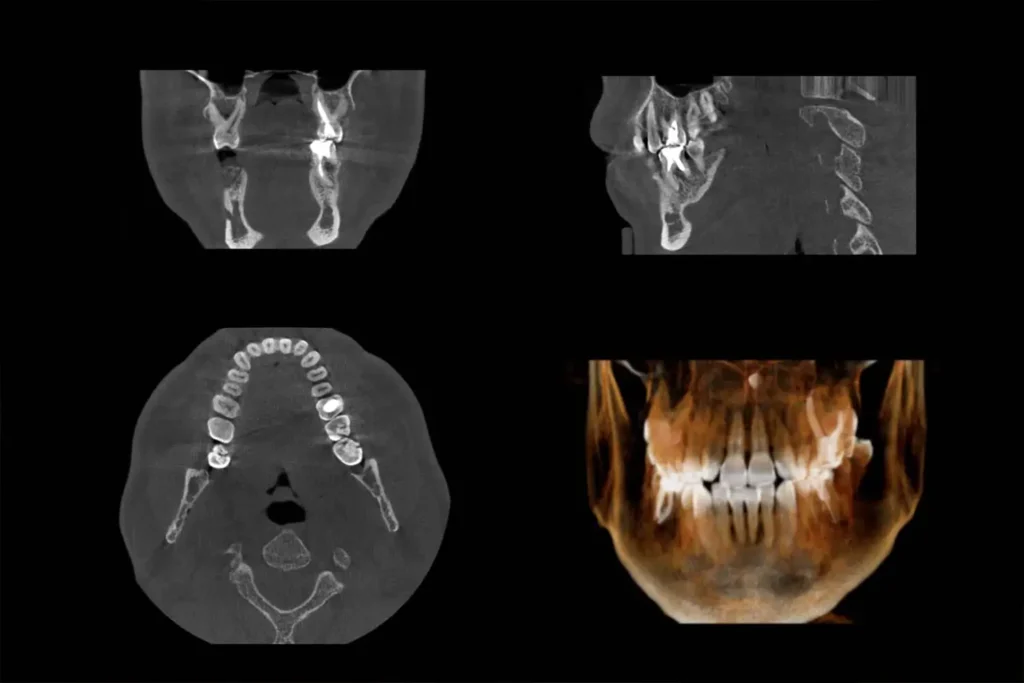

CBCT (Cone Beam Computed Tomography) provides detailed 3D images of teeth and surrounding structures, aiding in precise diagnosis and treatment planning for root canals.

With high-resolution 3D images, CBCT exposes hidden canals, fractures, or calcifications, ensuring accurate diagnosis and treatment planning.

There are several key differences between CBCT and x-rays. One is that a CBCT is capable of showing soft tissue, in addition to bone, in the same image. Also, it shows both in greater detail than x-rays are able to provide of just bone. Finally, a CBCT, as opposed to x-rays, only leaves the most minimal amount of radiation behind.

CBCT in endodontics offers a major advantage: 3D imaging. This enhances evaluation, diagnosis, and treatment, akin to a medical CT scan. It detects cracks, unusual anatomy, and diseases with greater detail and efficiency than traditional CT scans, requiring just one rotation around the patient’s head.